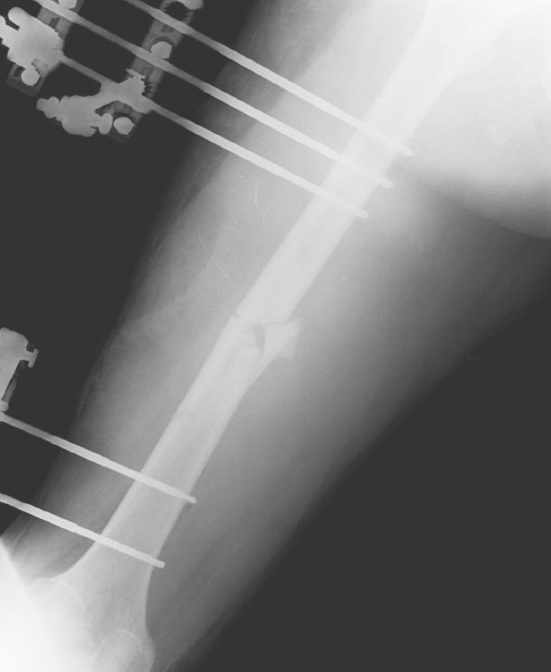

FIGURE 65.5 Damage control orthopedics consisted of rapid debridement of the open femoral fracture plus temporizing external fixation to achieve restoration of femoral length and alignment and decrease ongoing injury secondary to release of inflammatory mediators.

FIGURE 65.6 On postinjury day 5, after adequate restoration of physiologic stability, the patient underwent removal of the temporary external fixator and definitive fixation of the femoral fracture using a reamed intramedullary nail. He was discharged to a rehabilitation facility 19 days after injury.